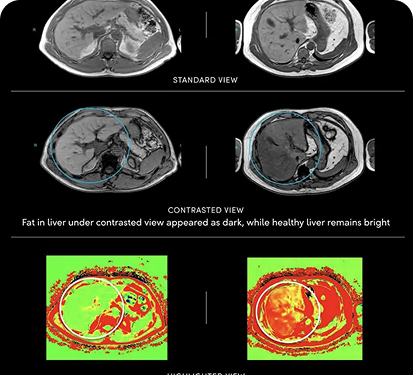

Comprehensive contrast-enhanced MRI examination of major organs and internal systems including neck, abdomen, liver, pancreas, and kidneys for thorough diagnostic evaluation.

We check for hundreds of detectable* conditions and can often detect solid tumors at Stage 1, and silent killers like aneurysms. Here are some of the conditions we can catch: